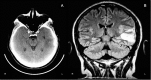

Although catatonia is a well-known psychiatric syndrome, there are many possible systemic and neurological etiologies. The aim of this case report was to present a case of a patient with cerebral venous sinus thrombosis and infarction in which catatonia was the clinical manifestation of a possible nonconvulsive status epilepticus. To our knowledge, only one such case has been reported in the literature, which had a simplified diagnostic investigation. It is important to correctly recognize the organic cause underlying catatonia in order to treat the patient as soon as possible thereby improving outcome. Therefore, physicians need to update their knowledge on catatonia, recognizing that it can be part of a psychiatric or neurologic condition.